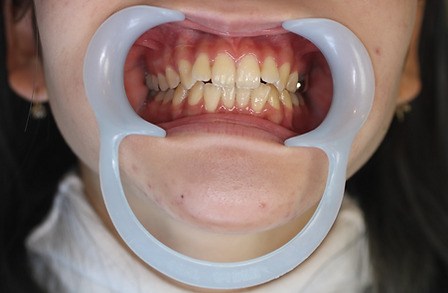

2ホワイトニング【治療例1】

治療前

治療後